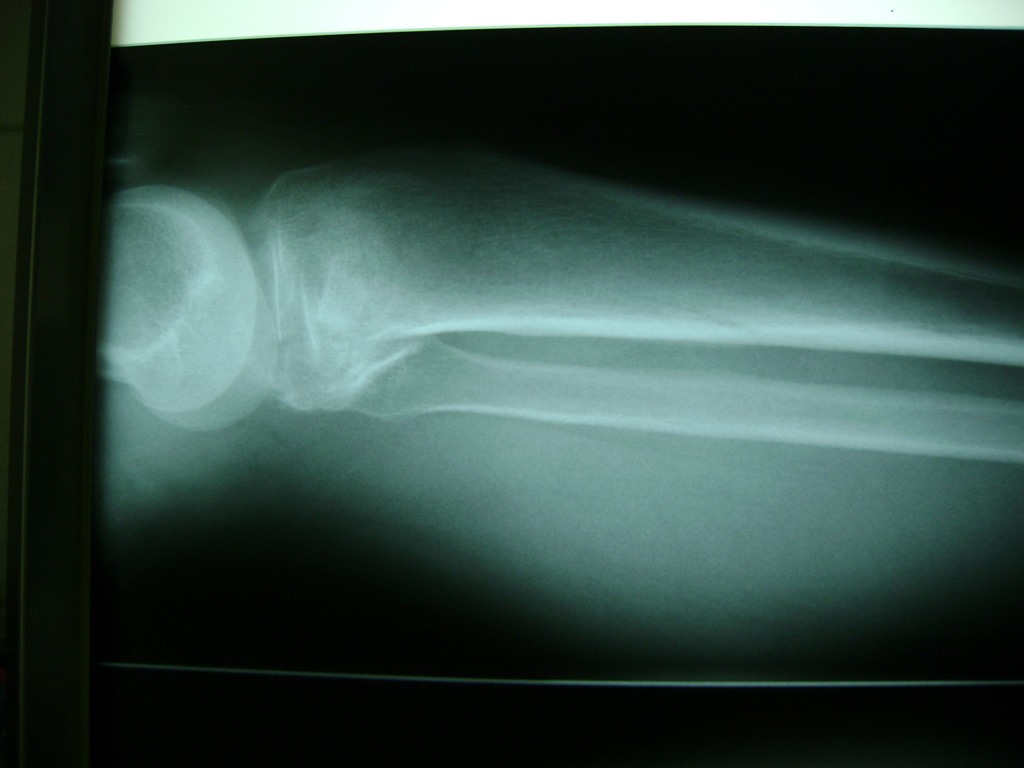

Cirugías de Peroné y Tibia

La artroscopia de rodilla es un cirugía en el cual la estructura interna de la articulación es examinada ya sea para realizar un diagnostico o para realizar un tratamiento, este procedimiento se realiza utilizando un instrumento parecido a un pequeño tubo llamado artroscopio.